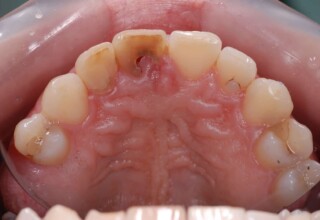

Δύσχρωμα απονευρωμένα δόντια

Μια ιδιαίτερη περίπτωση δύσχρωμων απονευρωμένων δοντιών που ο κεντρικός είχε βλάβη από εξωτερική απορρόφηση. Έγινε καθαρισμός του κεντρικού από την βλάβη και επειδή δεν μπορούσε να λευκανθεί λόγω της επαφής με τα ούλα, σφραγίστηκε σε πρώτη φάση, μετά λευκάνθηκε και στο τέλος έγινε η τελική αποκατάσταση.